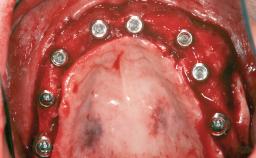

Le Fort I Interpositional Graft and Mandibular Sandwich Osteotomy for Maxillofacial Rehabilitation after Severe Periodontitis

A 47-year-old woman who had suffered from aggressive periodontitis requiring a number of periodontal interventions over more than 10 years was referred by her general dental practitioner and periodontologist for bone augmentation and implant therapy. Her failing dentition had already been scheduled for extraction. The patient expressed a desire for implant-supported fixed restorations and esthetic improvement of her lower face. She had agreed to consult with a maxillofacial surgeon after the referring dentist had suggested bone augmentation. An initial examination by the maxillofacial surgeon revealed mobility of all residual teeth in a patient who was very unhappy with the function of her removable partial dentures. Due to periodontally migrated flaring teeth and loss of occlusal support, the vertical dimension of occlusion was dramatically reduced. The patient was displeased with her lower face because of deepened nasolabial, commissural, and supramental folds.

# of Implants 14

Type of Implants Two-Piece

Defining Characteristics Fully edentulous upper jaw to be rehabilitated with four or more implants

Modality Fixed hybrid bridge on 5+ implants